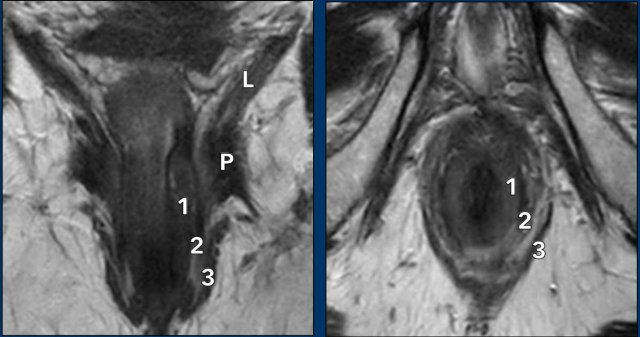

These images are of a patient with anal cancer.

Images

The MRI shows a clearly enlarged node (1.5 cm short axis diameter) adjacent to the internal iliac vessels, which was staged as N+ on MRI.

FDG-PET CT showed pathologic FDG uptake in the node, confirming it as N+.

In this case there are two small lymph nodes in the mesorectum that were considered as indistinct on MRI.

FDG-PET showed clearly increased FDG uptake in these small nodes, showing the added benefit of PET over MRI to stage anal cancer nodes.

The patient was finally staged as T2 N1a.